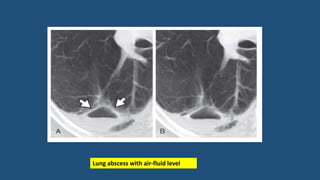

Lung abscess and cavities

• The hallmark of a lung abscess is necrosis or cavitation within an area

of pneumonia or dense consolidation.

• Commonly visible on CECT as one or more areas of low attenuation

within opacified lung.

• Cavitation is said to be present if air is visible within the lesion

Lung abscess with air-fluid level